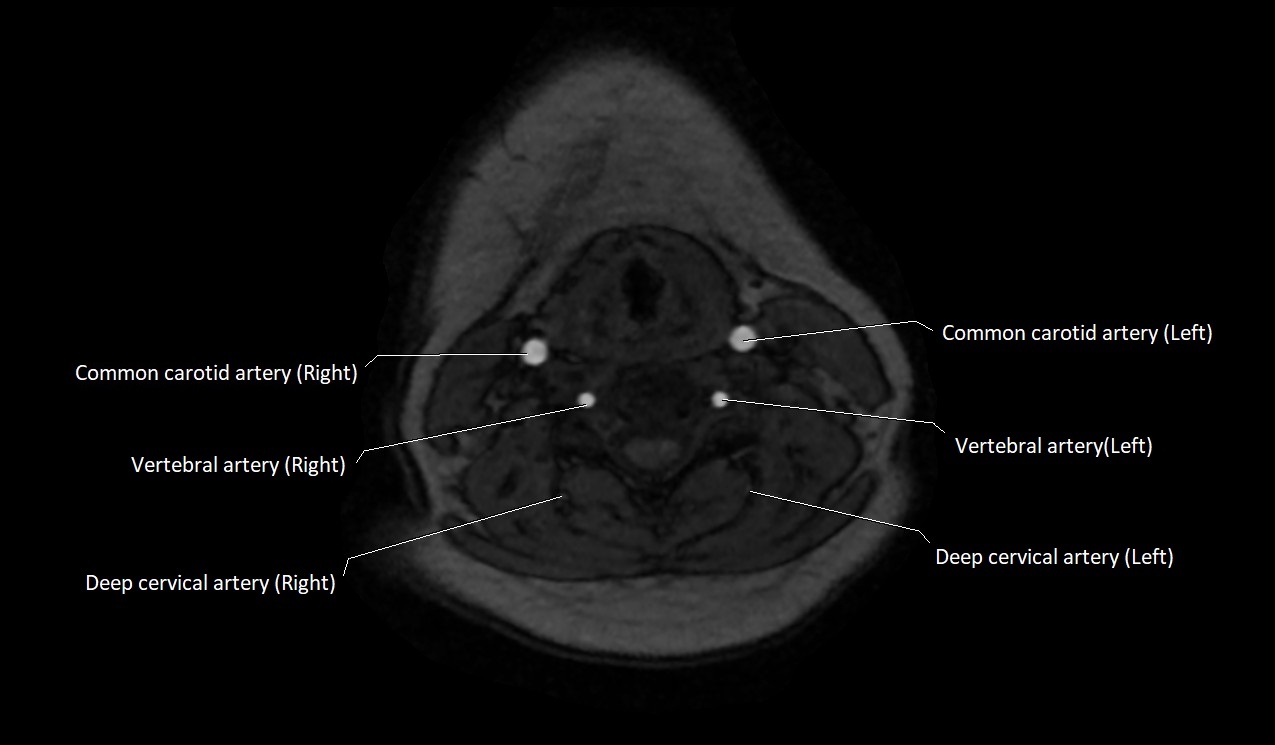

CT image

image